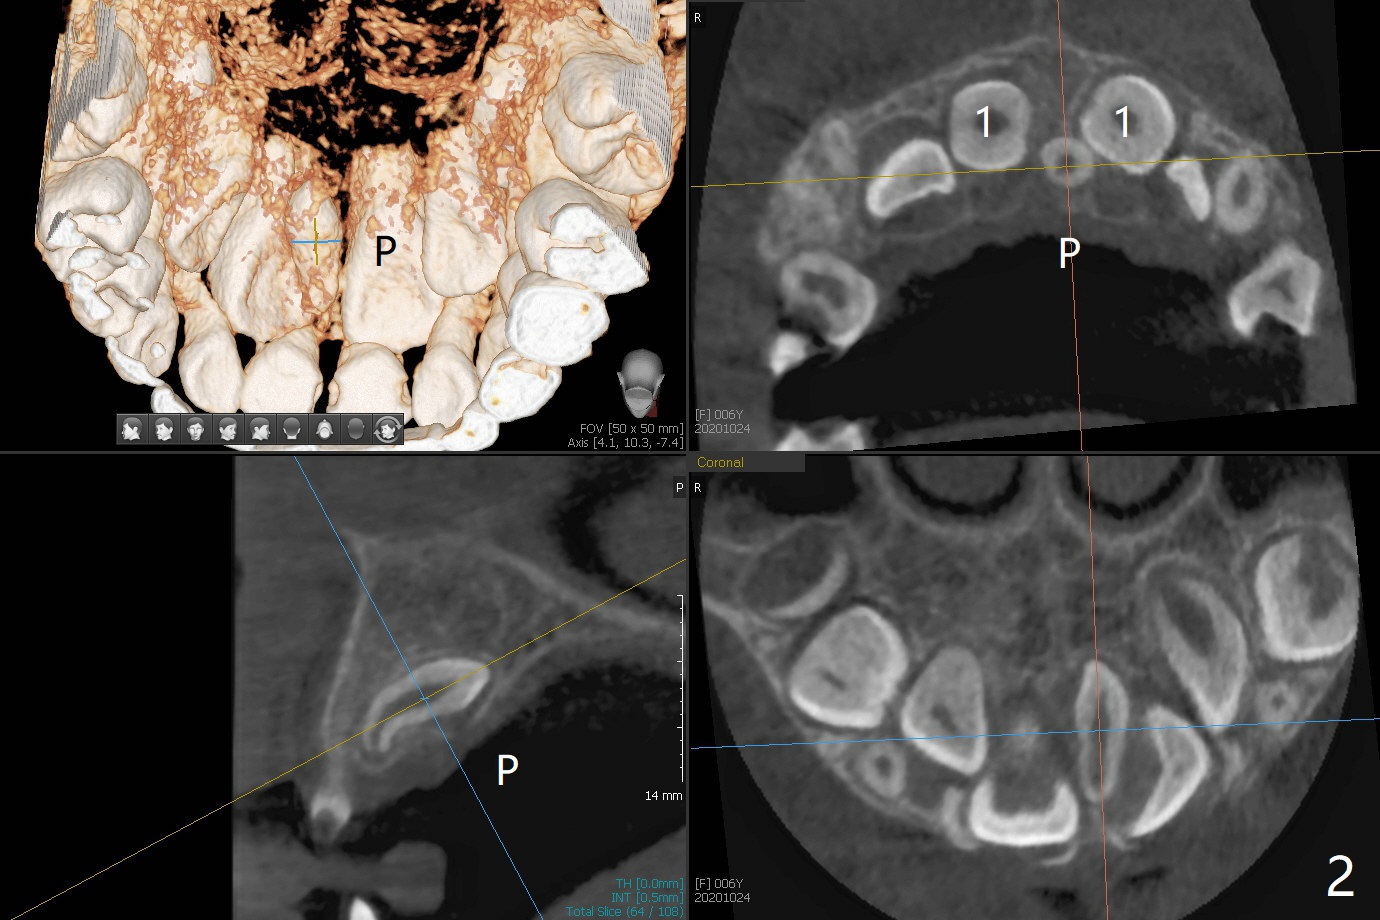

腭侧多生牙

6岁11月女上乳中切牙松动许久,但不脱落,根尖片显示正中多生牙(图一:M),CT显示后者位于腭侧(图二:P)。Take preop photos to show whether the lower lateral incisors have erupted or not. If yes, remove the upperdeciduous central incisors. 一个月后病人回来时,右上乳中切牙已脱落,左上松动 ,术中后者好像影响视野而拔除,腭侧切口,暴露左上1后,拔除多生牙(图三)。 术后3个星期左上中切牙萌出,扭转,反合(图四,五)。术后六个月仍旧如此(图六,七),右上中切牙未萌出,小孩害怕促进萌出手术。准备制作活动矫正器。